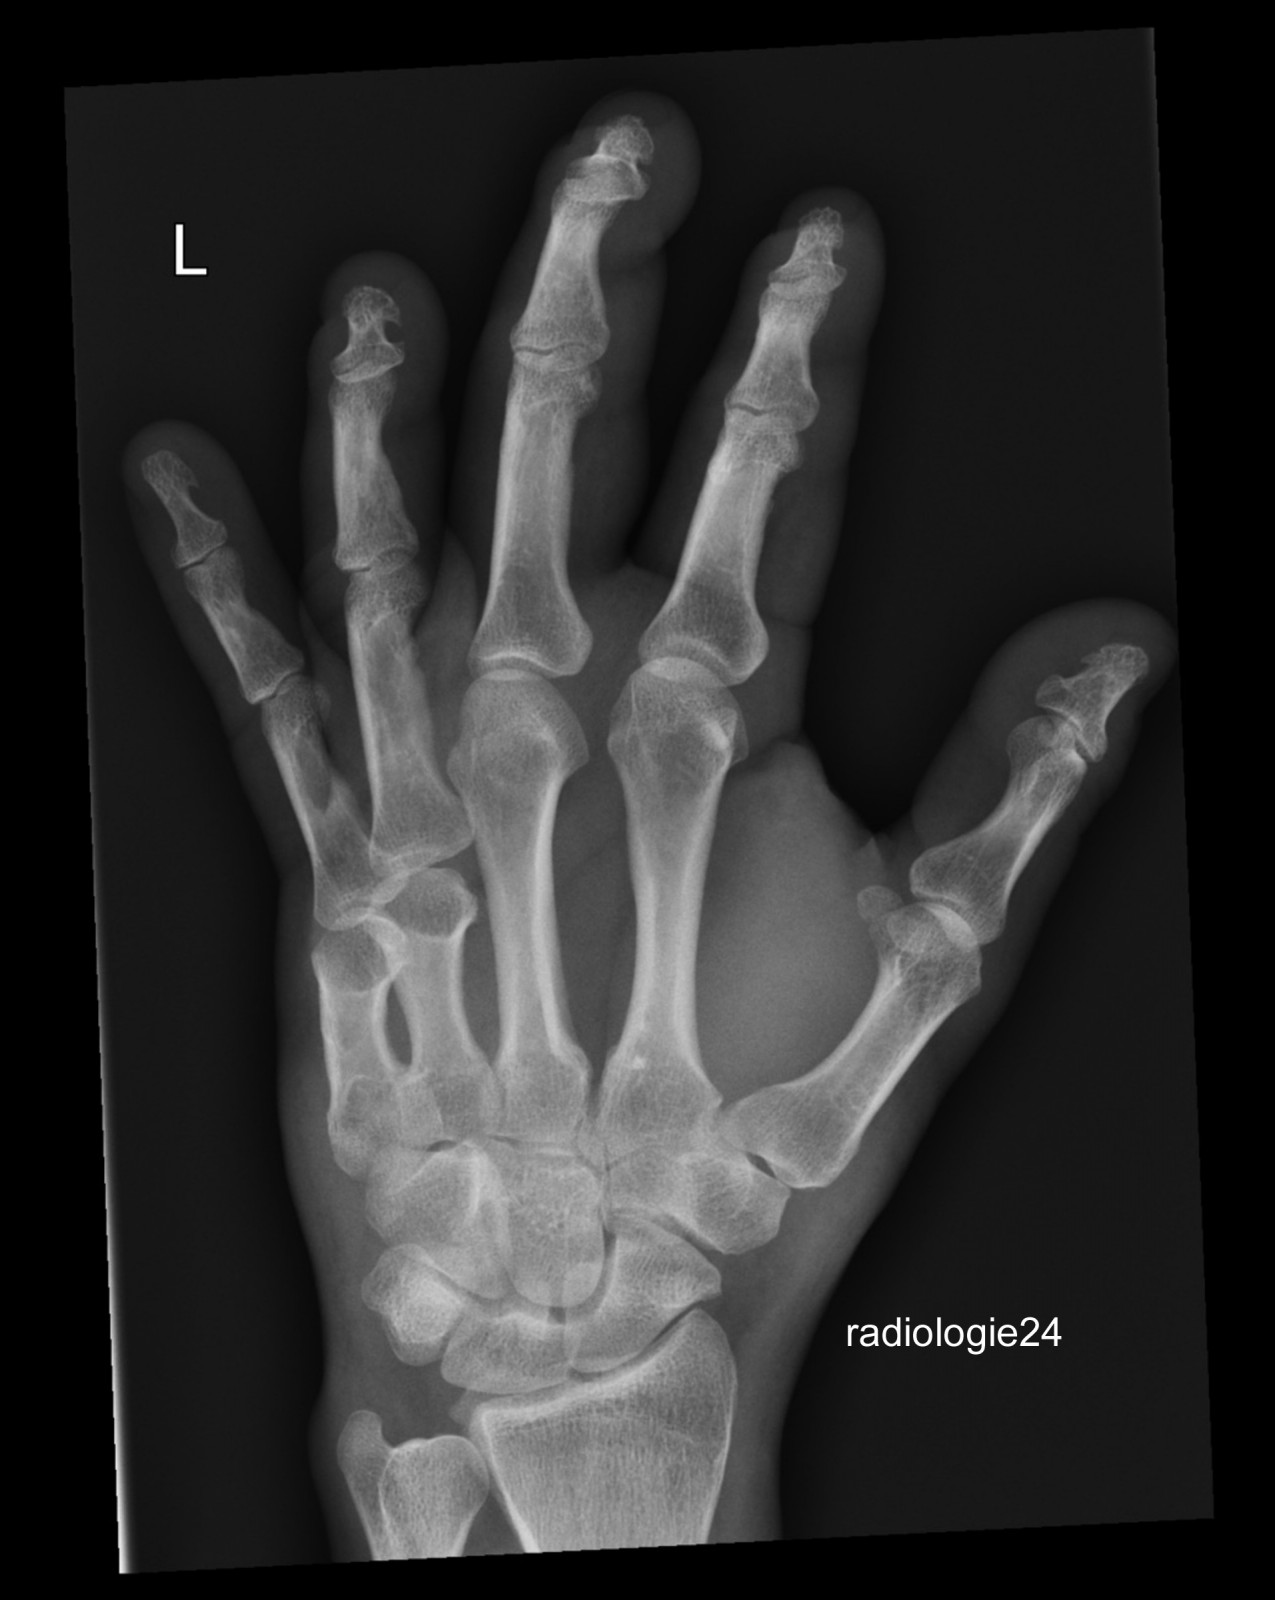

Röntgenfall des Monats Juni 2018 mit Auflösung

45 jähriger Patient Z.n. Sturz. Schmerzen Metacarpalia II/III. Fraktur? Ihre Diagnose?